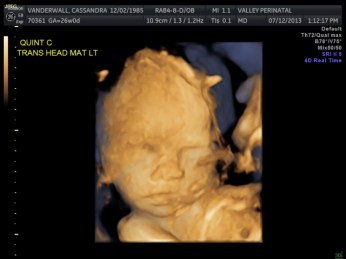

Friday we surpassed yet another milestone! The babies have been cooking for 7 months, which means we are now above the average gestational age for quintuplets. All of the babies were measured on Friday and they are all measuring within a day or two of the recommended size for babies at this point in pregnancy.

All of their organs (kidneys, bladders, hearts, brains, stomachs) look great and are also appropriate sizes. The blood flow to Elle has improved and has stabilized. All heart rates remain within normal limits, and are often on the higher side, which is probably because they just can’t sit still. We are truly excited to meet our little wiggle worms!